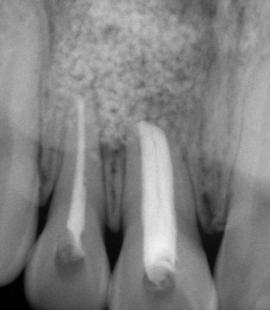

Figura 1. Se muestra una lesión extrusiva en los órganos dentales 21 y 22. Tomado de Aline Satie Takamiya y colaboradores en Iranian Endodontic Journal, Vol:4, Número:17, Año: 2022

Las lesiones traumáticas de los dientes permanentes son comunes y afectan entre el 10.5% y el 17.3%. La extrusión, la luxación lateral y la intrusión se encuentran entre los tipos más graves de traumatismo dental que pueden alterar el suministro vascular a la pulpa. Radiográficamente, las partes apical y lateral del alvéolo parecen vacías y, en general, el espacio del ligamento periodontal está agrandado. La obliteración del canal pulpar (OCP) y la necrosis pulpar (NP) son las consecuencias más frecuentes de la luxación extrusiva, mientras que la reabsorción radicular (RR) es menos frecuente. Las complicaciones dependen de factores como la gravedad de la lesión, el estadio de desarrollo radicular y la presencia de una alta carga bacteriana bucal. Las complicaciones pulpares y periodontales son más frecuentes en dientes con raíces completamente formadas que en ápice abierto. La prevalencia de obliteración del canal pulpar (OCP) como consecuencia de lesiones por avulsión y luxación está entre el 3 y el 24%. Por el contrario, es muy poco probable que los dientes con ápice cerrado presenten revascularización y a menudo desarrollan

necrosis pulpar. Las lesiones por luxación extrusiva requieren un tratamiento inmediato, consistente en reposicionamiento y estabilización. El tratamiento comienza con un correcto diagnóstico clínico y radiográfico, seguido del reposicionamiento manual del diente en el alvéolo y la colocación de una férula flexible, para permanecer in situ durante aproximadamente 2 semanas.6

3. Radiografía periapical de una luxación extrusiva en el órgano dental 11

Trauma en niños y adolescentes: luxaciones

Figura